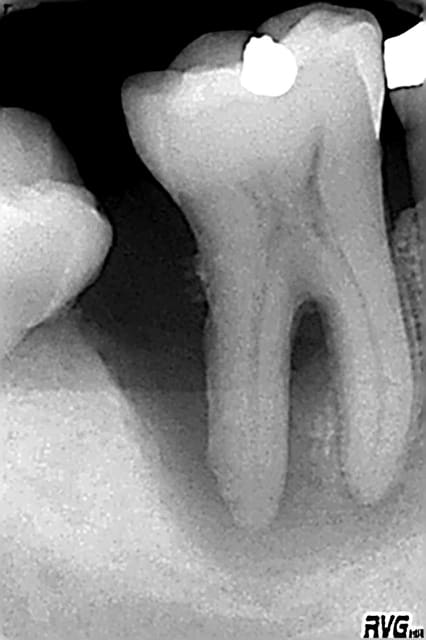

Est-ce un fruit du hasard, mais les interventions que j'ai négociées représentent pratiquement tous les cas de figure qu'a traité Stéphane:

- fausse route bouchée au MTA

-instrument fracturé impossible à retirer, je suis passée à côté et je l'ai noyé dans la gutta chaude.

Et tout de même quelques racines domptées sans trop de difficultés!